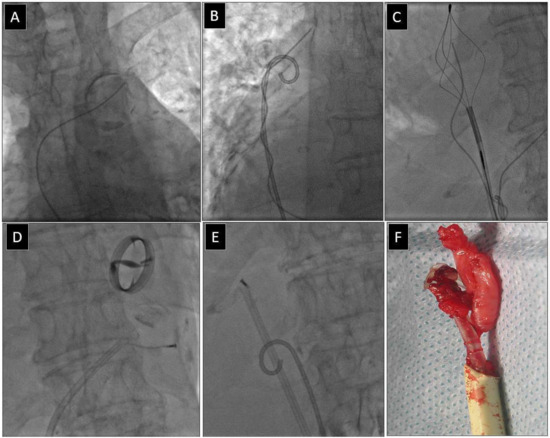

2.2.5. Extraction of Leads with Their Proximal Ends Migrated into the Cardiovascular System